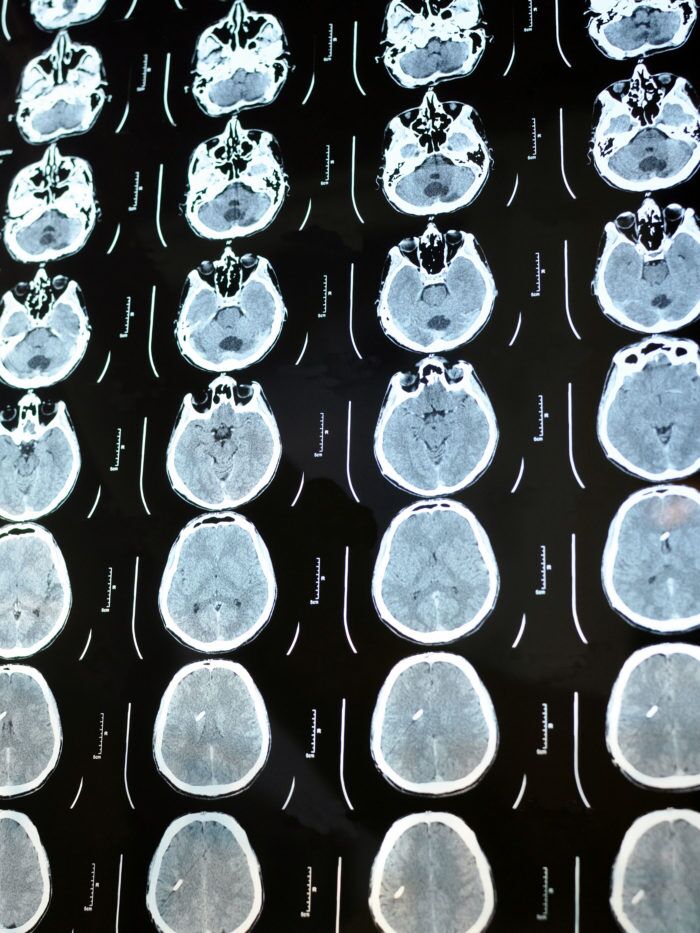

Hydrocephalus Treatment

We know that as parents you want the best possible care for your child, especially when they have a complex condition. CHOC is the region’s leader in treating complex multicystic hydrocephalus. Our neurosurgeons have pioneered many unique procedures to ensure the most cutting-edge treatment possible for kids with hydrocephalus. We are here for your child and your family through every step of hydrocephalus treatment and are committed to delivering care tailored to your needs.

- At CHOC, we are the region’s leader in treating complex metacystic hydrocephalus for children and babies. Our neurosurgeons have pioneered many unique treatments, including a valve that is implanted in the brain and drains fluid, and an endoscopic third ventriculostomy, which involves making a tiny hole in the wall of the third ventricle, allowing fluid to move out of the blocked ventricle and eliminating the need for a valve.